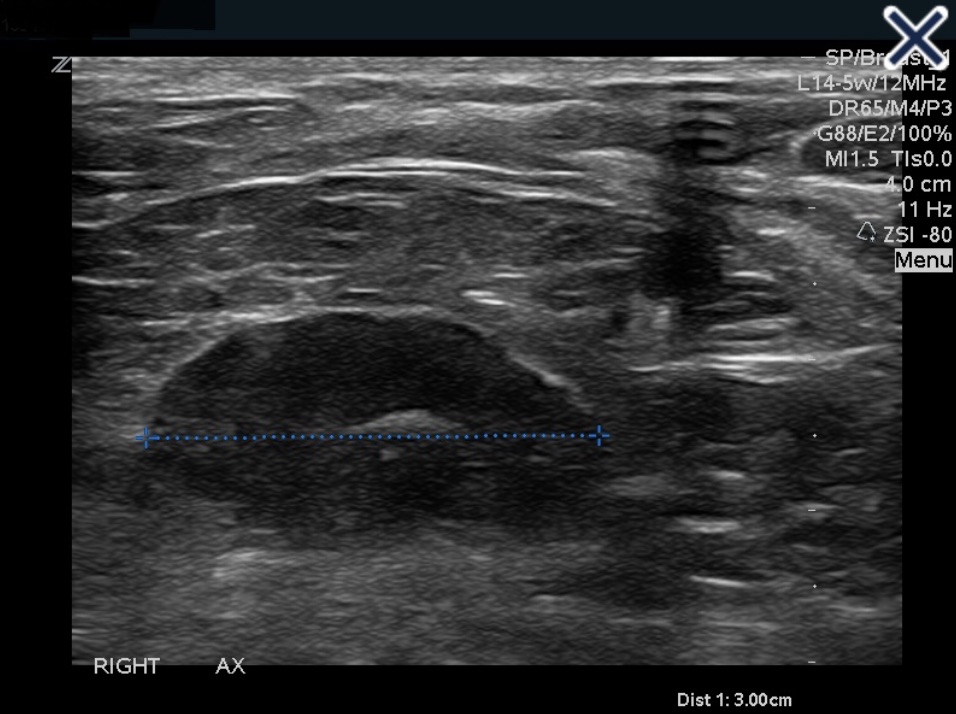

• Reactive nodes can be difficult to distinguish from metastatic nodes (Image)

• In general, benign causes of nodal enlargement:

• Tend to thicken the cortex diffusely

• In addition, it is not uncommon to have a metastatic node adjacent to a normal node:

• But all nodes in a region tend to be reactive when the cause is benign

• Finally, a reactive node has blood supply on Doppler examination through a single hilum, whereas metastatic nodes tend to have multiple transcapsular vessels